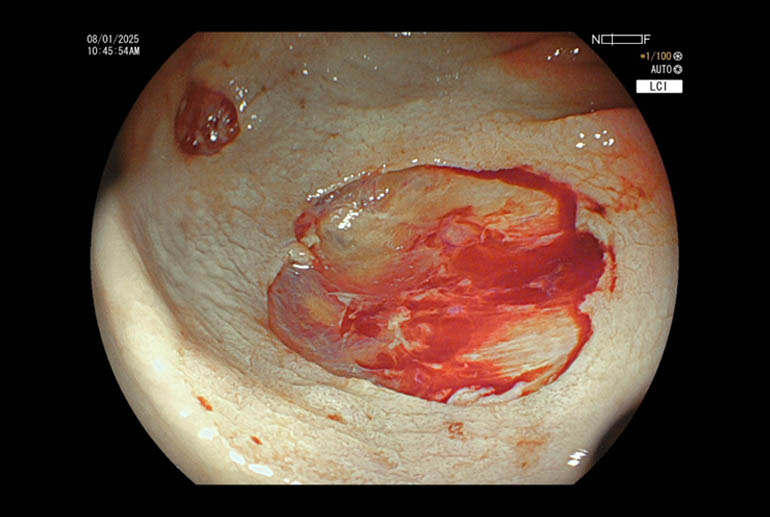

Performing the same procedure under water is now recognized to offer additional advantages. In this technique then a polyp is detected, air is sucked out of the colonic lumen and approximately 300 to 400 mL of water is infused. The entire procedure of snaring and resecting the polyp is then done under water immersion. Water acts as a natural magnifier hence mucosal details of the polyp are much more clearly visualized. Most polyps tend to float in water due to their fat content and this leads to a natural separation of the polyp from the underlying submucosal layers. This makes it easier to grasp the polyp by snare and to resect it with less possibility of causing a perforation.

Our patient had multiple polyps ranging between 7mm to 15 mm. Most of the polyps were flat, classified as Paris to AA. Several of these polyps were situated in cecum and ascending colon where colonic wall is quite thin and risk of perforation is higher. Using the technique of hydraulic immersion, it was possible to remove all these polyps with minimal risk to the patient. Post polypectomy site of the largest removed polyp was seen to be oozing blood; this was sealed with application of 3 hemoclips; effective hemostasis was achieved and patient did not suffer any complications.